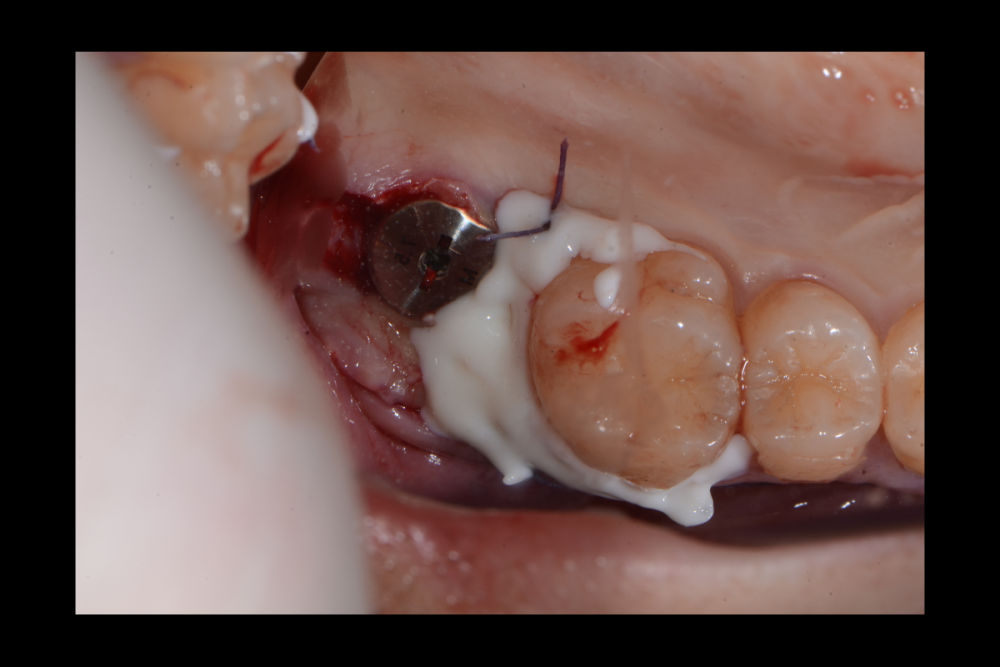

Карен Аванесов Опубликовано 20 сентября, 2021 Поделиться Опубликовано 20 сентября, 2021 (изменено) одномоментной установки имплантата, без вторжения в верхнечелюстной синус, регионарная мягкотканная пластика, выгодная ортопедическая ангуляция, не выгодной небной лунки. Пустоты заполнены губкой дигестол, дополнительная герметизация ликвидам. Мой только хирургический протокол, пациент реферативный. Время работы от удаления до имплантации 40 минут, ожидание до протезирования 3 месяца. Кейс посвящаю одноглазому и зеленому хулигану, любителю пива и девок, не знаю куда он делся, но пусть не грустит, все будет хорошо! Изменено 20 сентября, 2021 пользователем Карен Аванесов 10 1 1 Ссылка на комментарий

Карен Аванесов Опубликовано 25 сентября, 2021 Автор Поделиться Опубликовано 25 сентября, 2021 22.09.2021 в 18:52, сирена сказал: Ок) Бум ждать. А длина импланта какая? 10х4.5 1 Ссылка на комментарий